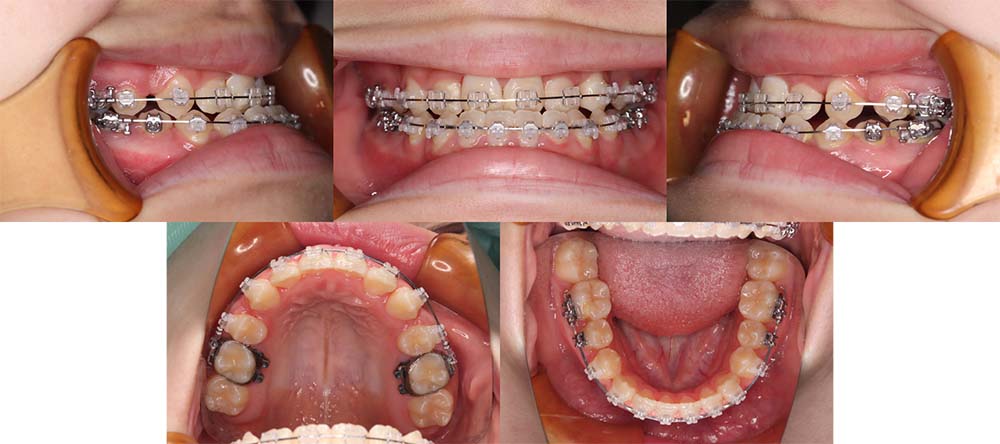

| 症例分類 | 顎変形症、叢生、開咬 |

| 診断名 | 上下軽度叢生を伴う骨格性開咬 |

| 主訴 | 前歯でものが噛み切れない、奥歯もあまり噛み合わない |

|---|---|

| 年齢 | 21歳9ヶ月 |

| 性別 | 女性 |

| 抜歯部位 | 上下左右の第一小臼歯(4本) |

| 使用装置 | 表側のワイヤー装置+外科矯正(手術を併用した治療) |

| 治療期間 | 1年8ヶ月 |

| 保定装置 | 固定式保定装置、取り外し式保定装置(8時間) |

| 費用 |

保険適応 [検査・診断等] 2万円程度 [装置装着] 5〜7万円程度 [調整料] 2,000〜7,000円程度/回 [手術前検査等] 2万円程度 [保定装置等] 4万円程度 合計18〜25万円程度 |

下顎の右側偏移があり、骨格的にも受け口だったため、上顎両側第一小臼歯を抜去して手術を併用して治療を行いました。術前は前歯が反対のかみ合わせになり、初診時より咬合、顔貌は一旦悪くなります。1年5ヶ月の術前矯正のあと手術を行いました。

手術後に使用が必要になるゴムの協力度が高く、手術後は7ヶ月の術後矯正で治療を終了することができました。

顎の歪みも下顎の前方感も改善することができました。